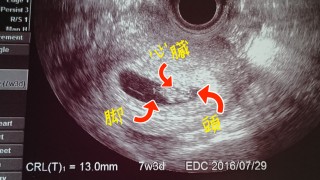

8w2dですが、赤chanの大きさ的に7w3d13mmとのことでした。 頭や脚の向きも教えてくれました。 2週間後…今年最後の検診で予定日決めましょう、って言われました。 その時に母子手帳も言われるかなぁ? 楽しみです(⌒‐⌒)